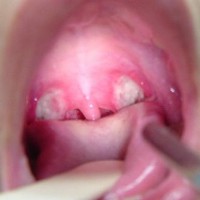

Een arts zal de amandelen goed willen bekijken en ziet snel of er sprake is van ontstoken keelamandelen. De keelamandelen zijn vuurrood en gezwollen, vaak zijn er ook witte plekjes zichtbaar. Over het algemeen is het niet nodig om aanvullend onderzoek te verrichten.